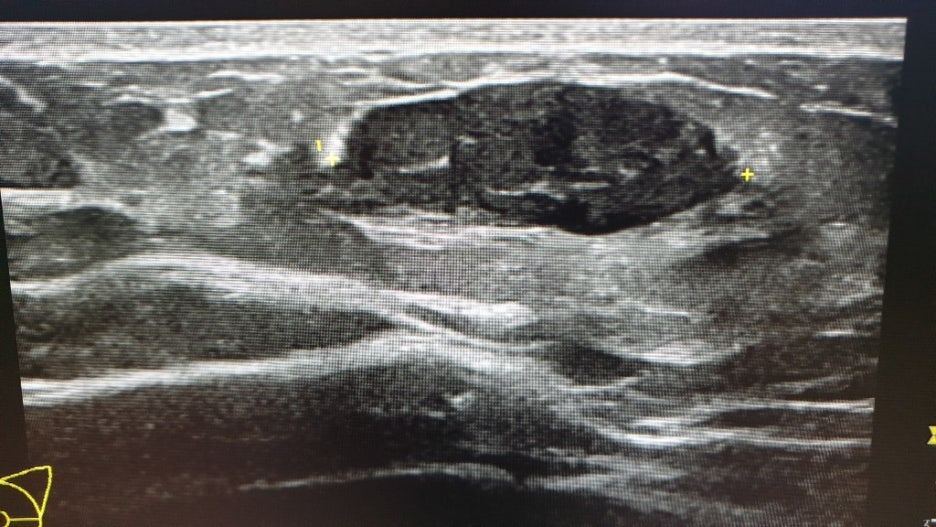

힐끗힐끗 화면을 보니 작고 둥근 것들이 보였고, 여러 번 길이를 재는 것이 보였어요. 엑스레이 상으로는 깨끗했던 오른쪽 가슴에도 혹이 보였어요. (점점 불안해지기 사작했습니다...)

왼쪽 2.3cm / 오른쪽 1.4cm + 기타 작은 혹 몇 개

크기보다 모양이 더 중요하다고 하더군요. 일단 동글동글하면 괜찮은 것이고 뾰족뽀족하게 생기면 악성일 가능성이 크다고 합니다.

모양이 나쁘지는 않지만 크기가 1cm 이상이면 작은 것은 아니므로 조직 검사를 하자고 하더군요. 조직 검사를 해서 이 혹이 어떤 혹인지 정확하게 확인 후 치료 방법 등을 생각해 보자고 하셨어요.